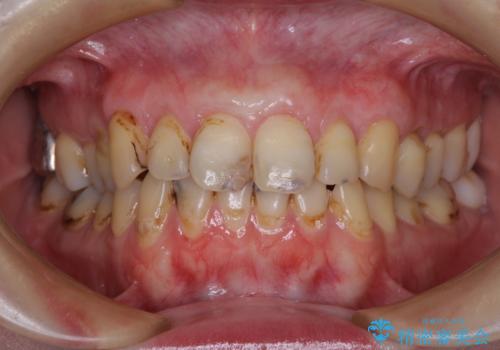

- 上下前歯や奥歯の虫歯治療を希望して来院された患者様です。

全顎的にむし歯が多く、根管治療の必要奥歯や、審美的に気になっている前歯を中心にオールセラミッククラウンにて補綴治療を行うこととしました。

上顎前歯は歯肉退縮により歯根が露出していたため、事前に歯肉移植術により根面被覆を行い、その後にオールセラミッククラウンを装着することとしました。